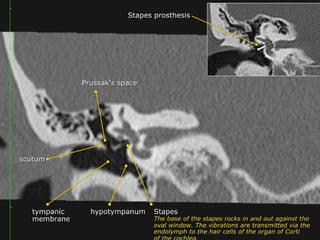

 Epitympanum (attic):

Middle ear above line from

scutum tip to tympanic

 Mesotympanum: Middle

ear proper

 Hypotympanum: Shallow

trough in floor of ME

Three compartments in coronal plane.

• A line drawn from lower edge of the scutum to the tympanic

portion of the facial nerve -epi/mesotympanum.

• parallel to the floor of the external auditory canal

meso/hypotympanum

-Prussak space (superior recess), this space is marginated by the pars

flaccida and scutum laterally, the lateral malleal ligament superiorly,

and the neck of the malleus medially

The base of the stapes rocks in and out against the membrane in the

oval window.

The vibrations are transmitted from the oval window via the endolymph

to the hair cells of the organ of Corti in the cochlea.

The round window dissipates the pressure generated by the fluid

vibrations within the cochlea and thus serves as a release valve.